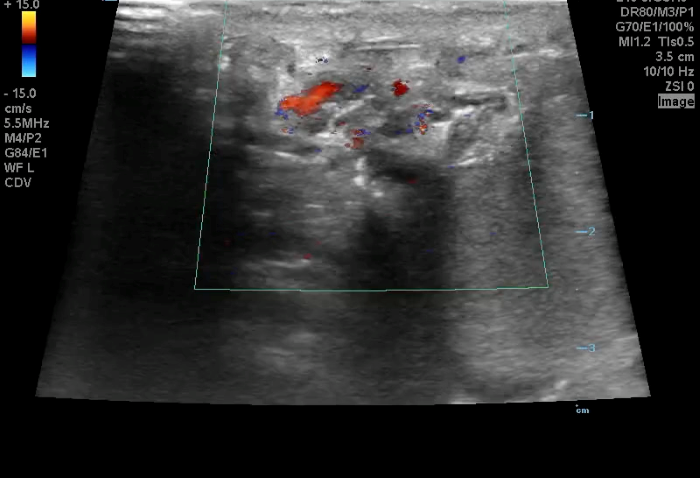

Torsion - Image 1_crop.pngImage 1. Color Doppler of a testicle without blood flow to the body of the testicle concerning for testicular torsion.

In your first image (Image 1), you realize there is no flow with color Doppler. Additionally, you find a torsed cord complex (Image 2), also known as the “corkscrew sign.” You consult Urology who is busy in the operating room with another case. You decide to perform a manual detorsion due to your concern for testicular atrophy and risk of infertility. Using the open book technique, you get relief of pain and return of vertical positioning of the testicle after two rotations. On your repeat testicular POCUS with color Doppler you obtain these images (Images 3 and 4), which demonstrate venous and arterial flow throughout the testicle. The cord is now untwisted and appears linear in orientation.